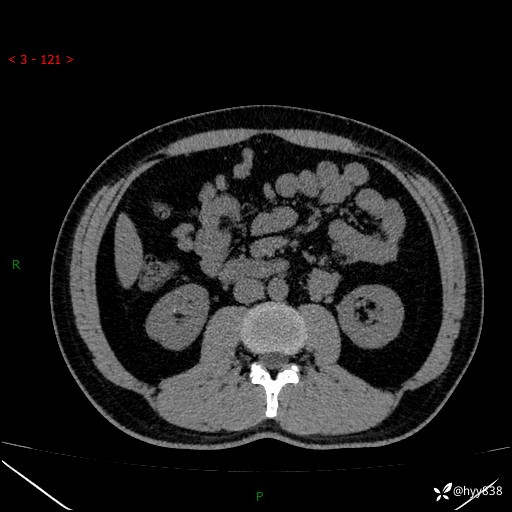

现病史:患者3月余前检查发现左侧腹膜后占位,大小约3.7*4.9cm,平素无腰疼,无肉眼血尿,无尿频尿急等不适,当时未特殊处理,在门诊复查CT提示左侧腹膜后占位,门诊拟“左侧腹膜后占位”收入院。 起病以来,患者精神佳,饮食、睡眠良好,大小便正常,体力体重无明显变化。

腹膜后CT平扫+增强